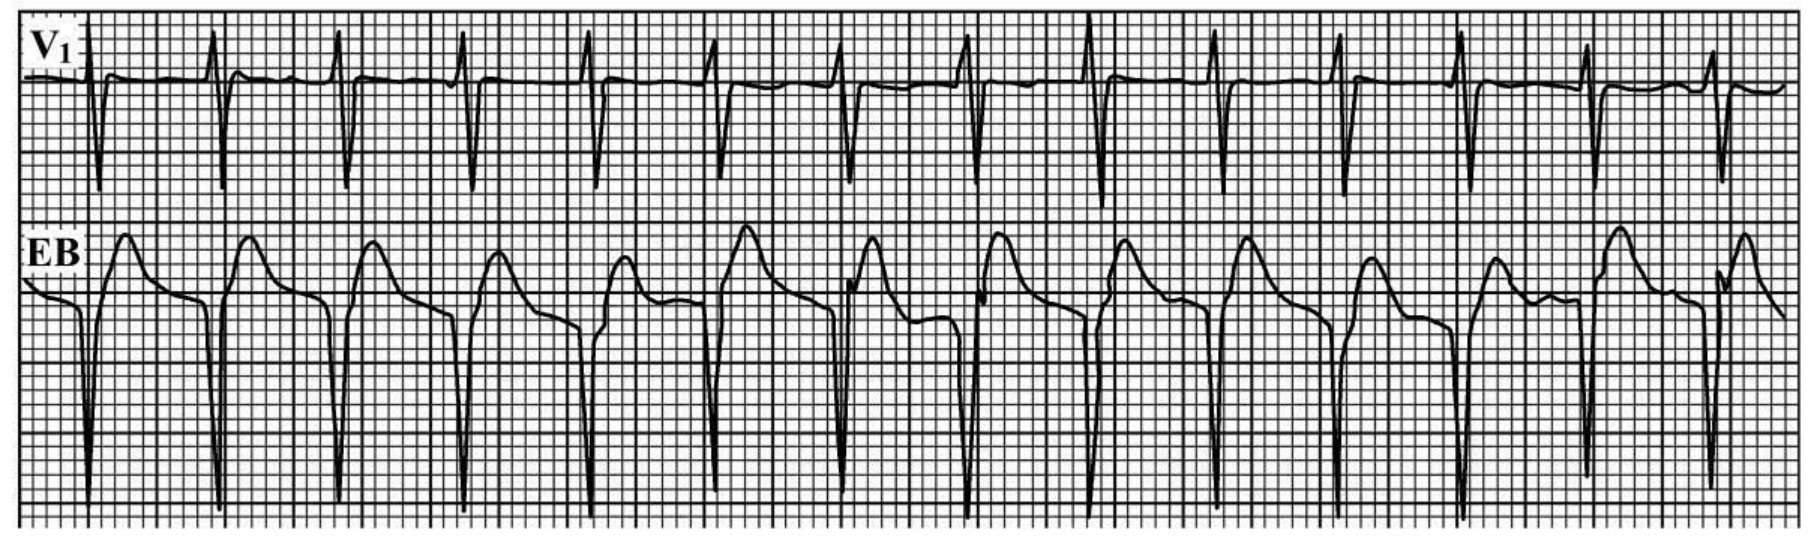

img1252

图60-90 下行为食管导联,V1导联QRS终末部有一假性r波,实为逆行P-波,显示慢—快型房室结内折返性心动过速

(三)出现慢—快型房室结内折返性心动过速,其P-R间期>R-P间期,R-P间期<0.08s(图60-90)。